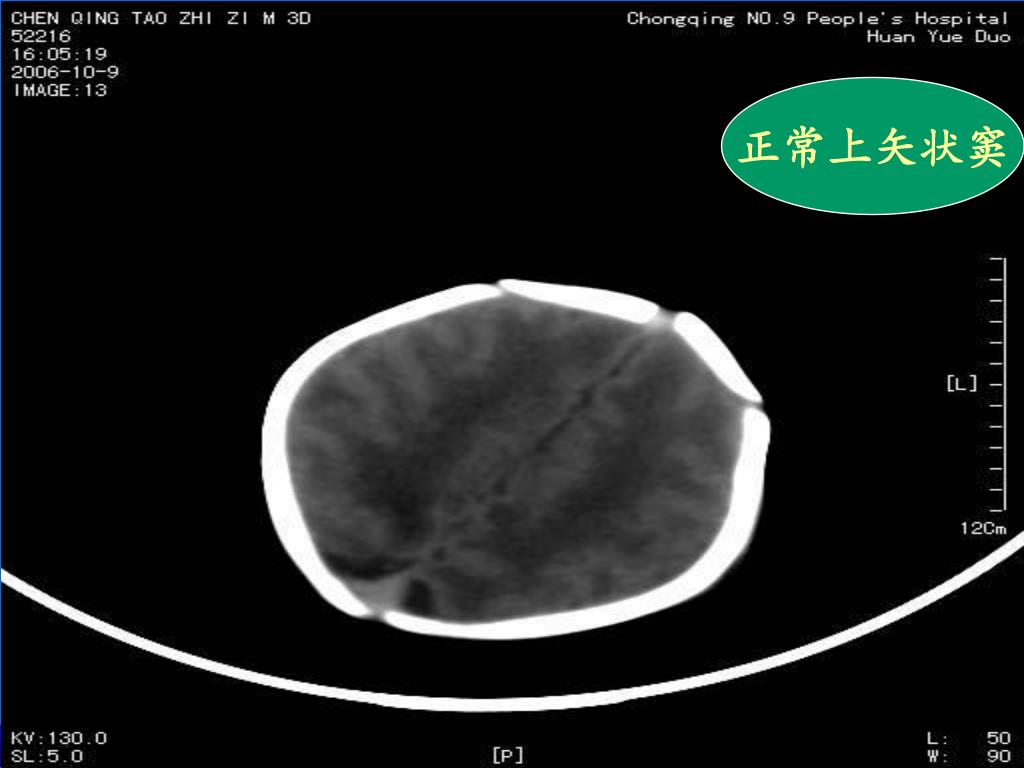

30. 正常上矢状窦

31. 正常上矢状窦

17. (3)正常新生儿的上矢状窦区CT表现为三角形高密度,密度均、边缘锐利,且无张力。新生儿蛛血时,此区边缘欠规整及张力升高,且其中心区可呈略低密度改变,是由于此区有新鲜出血与局部静脉窦有密度差值所致--空三角征;此为诊断该区蛛血的重要征象。(3)正常新生儿的上矢状窦区CT表现为三角形高密度,密度均、边缘锐利,且无张力。新生儿蛛血时,此区边缘欠规整及张力升高,且其中心区可呈略低密度改变,是由于此区有新鲜出血与局部静脉窦有密度差值所致--空三角征;此为诊断该区蛛血的重要征象。